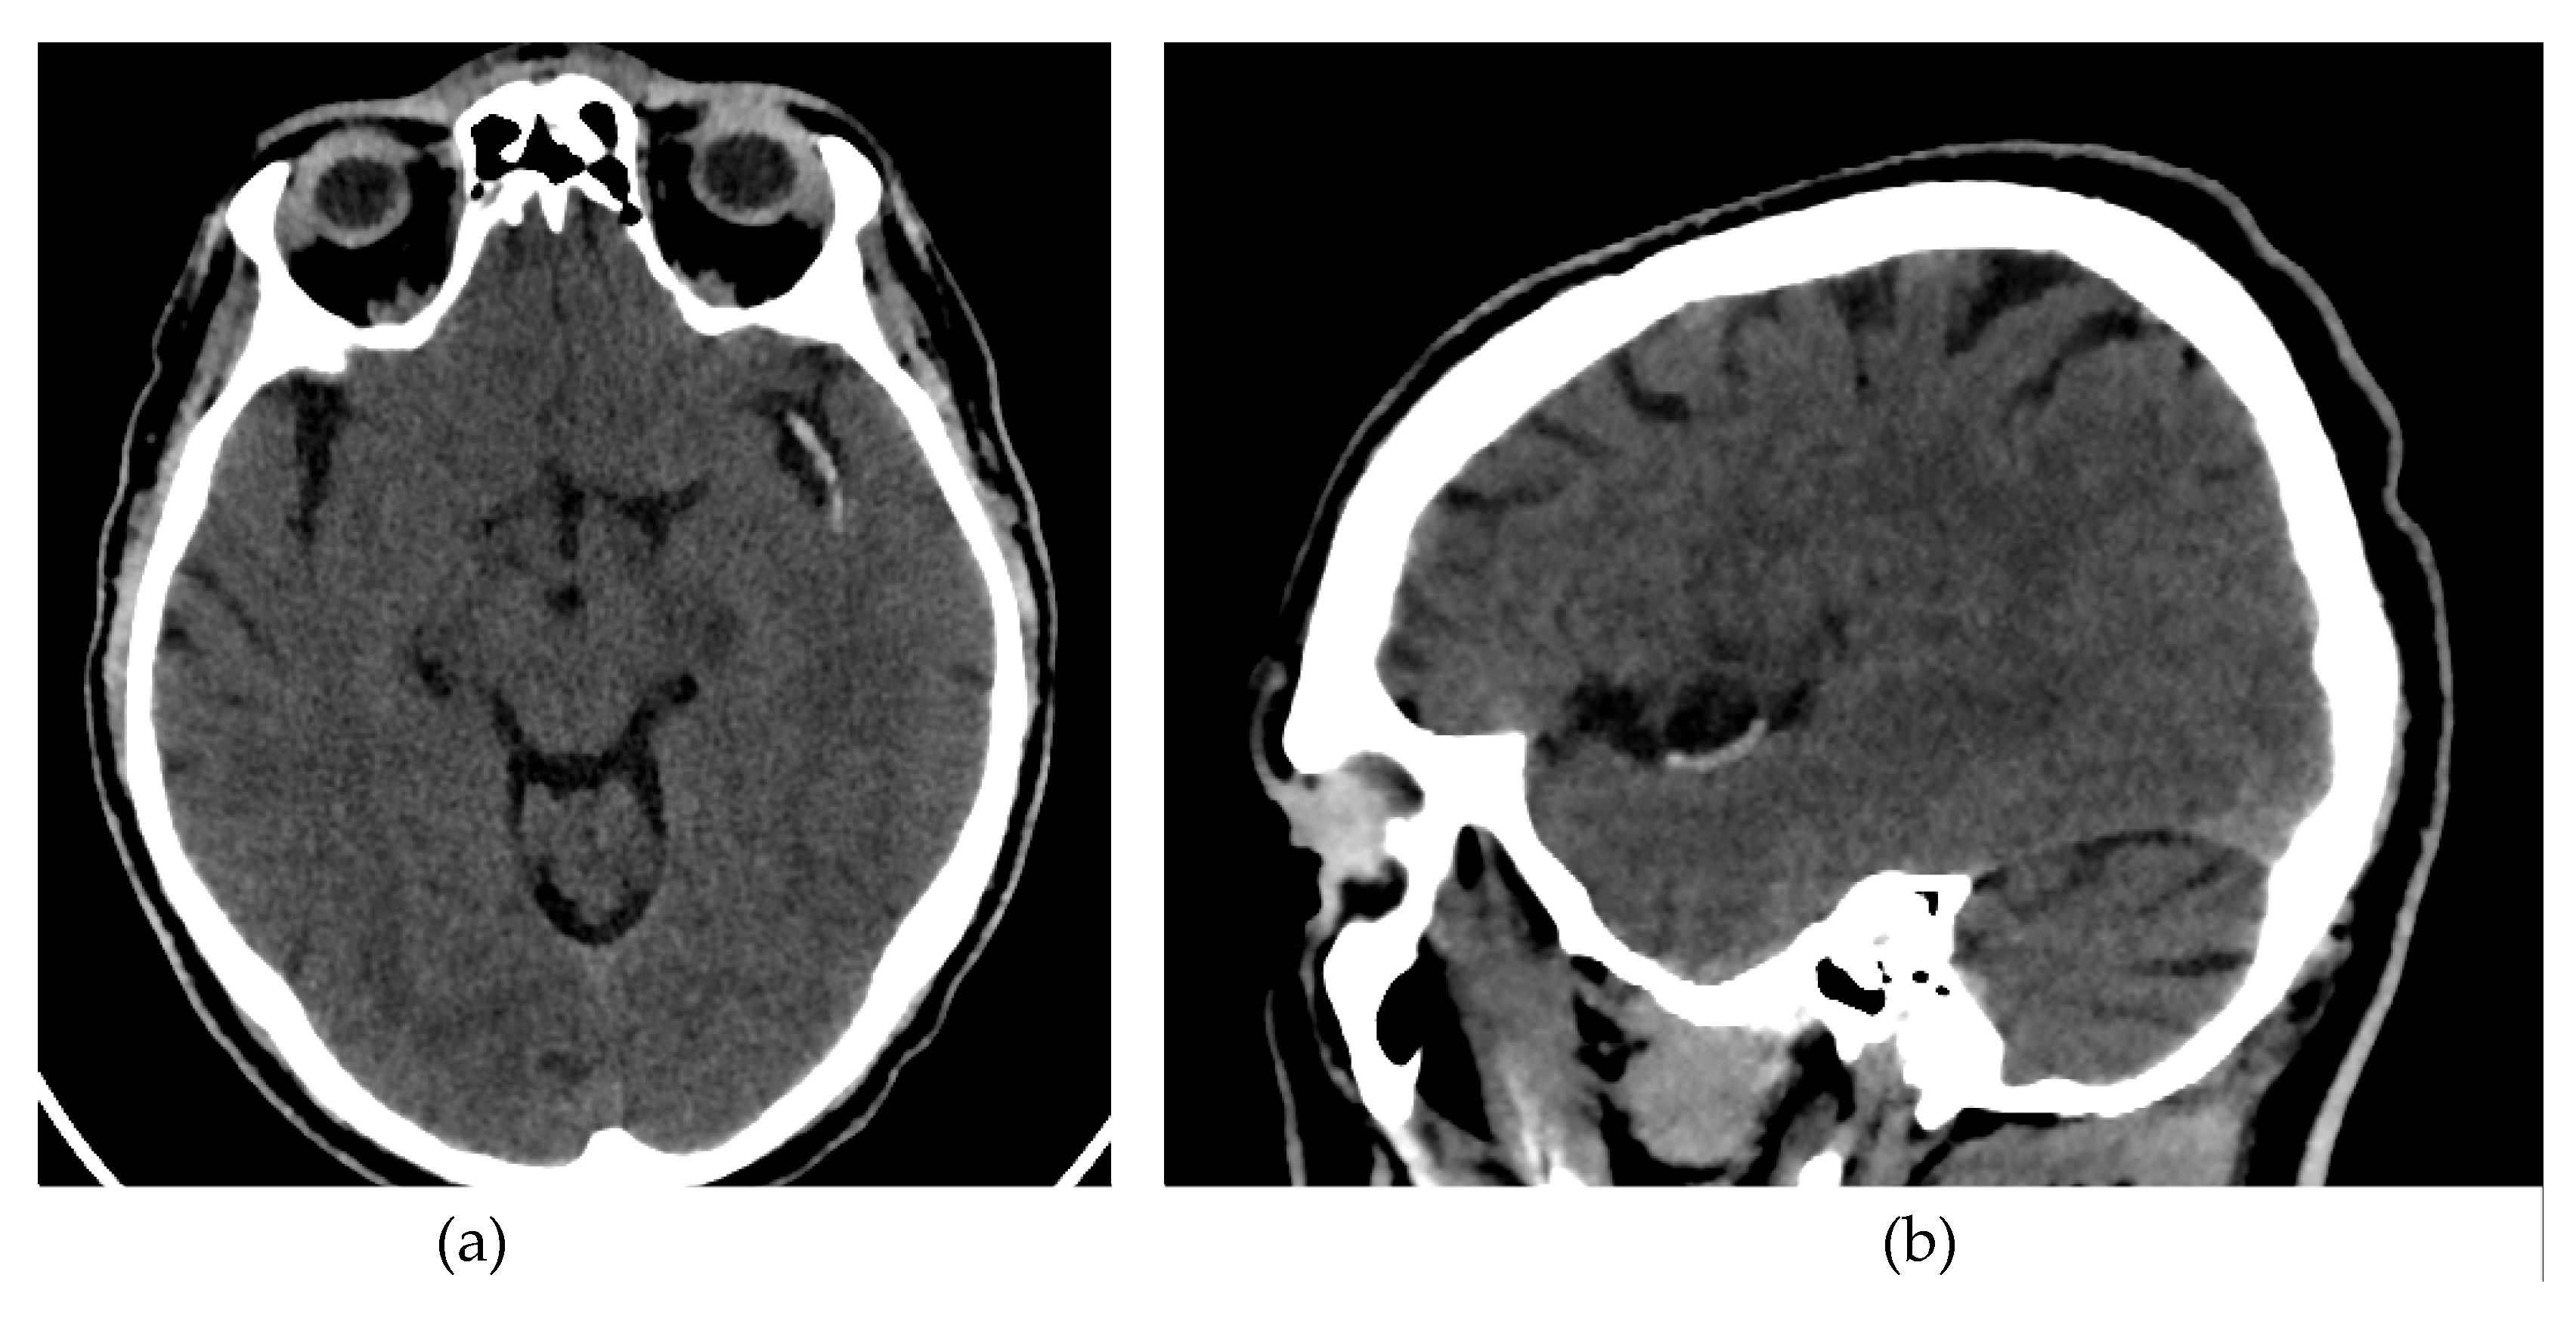

All patients enrolled in the study underwent a NCCT at our hospital using two different CT scanners (16 rows of detectors, 120 kV) of the same make and model (Phillips Ingenuity; Amsterdam, Netherlands) during the diagnosis process of AIS. Patients were randomly assigned to each scanner. The images obtained had a slice thickness of 0.625 mm. Although reconstructions with a thickness of 1 mm were available, they were not used for analysis. The window width and center were set at 80 and 40 Hounsfield units, respectively (Figure 1).

Figure 1. Brain NCCT of a patient with AIS and the hyperdense MCA sign. This is one of the radiological signs of AIS in NCCT. (a) Axial NCCT scan of a patient with a hyperdense left MCA sign. (b) Sagittal NCCT scan of the same patient.